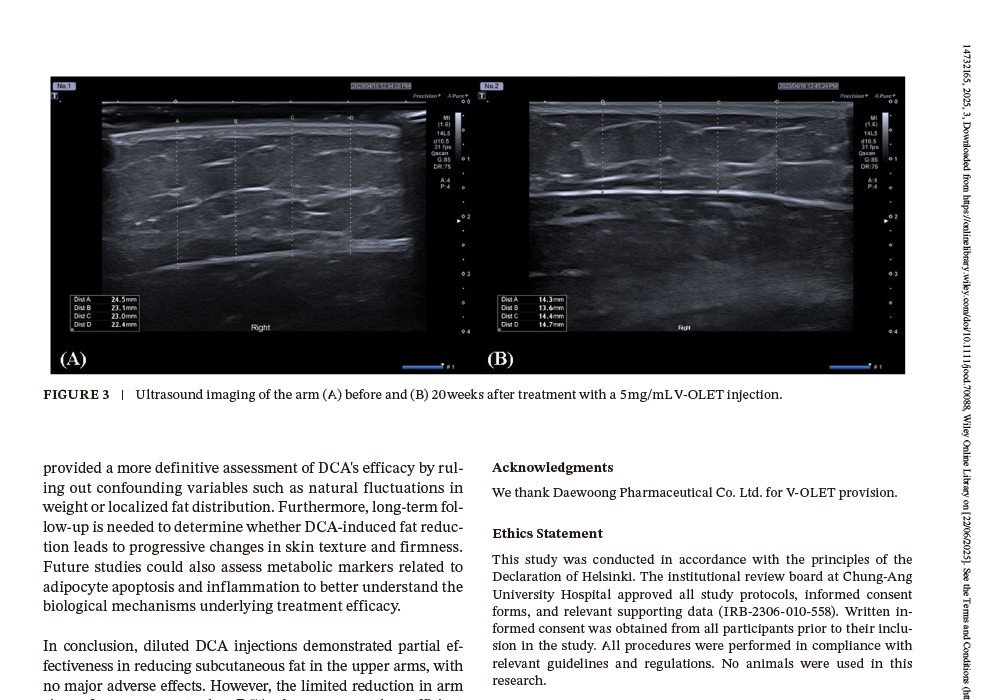

Fat thickness (via ultrasound):

2.5 mg/mL: 4.68 mm reduction

5 mg/mL: 7.49 mm reduction